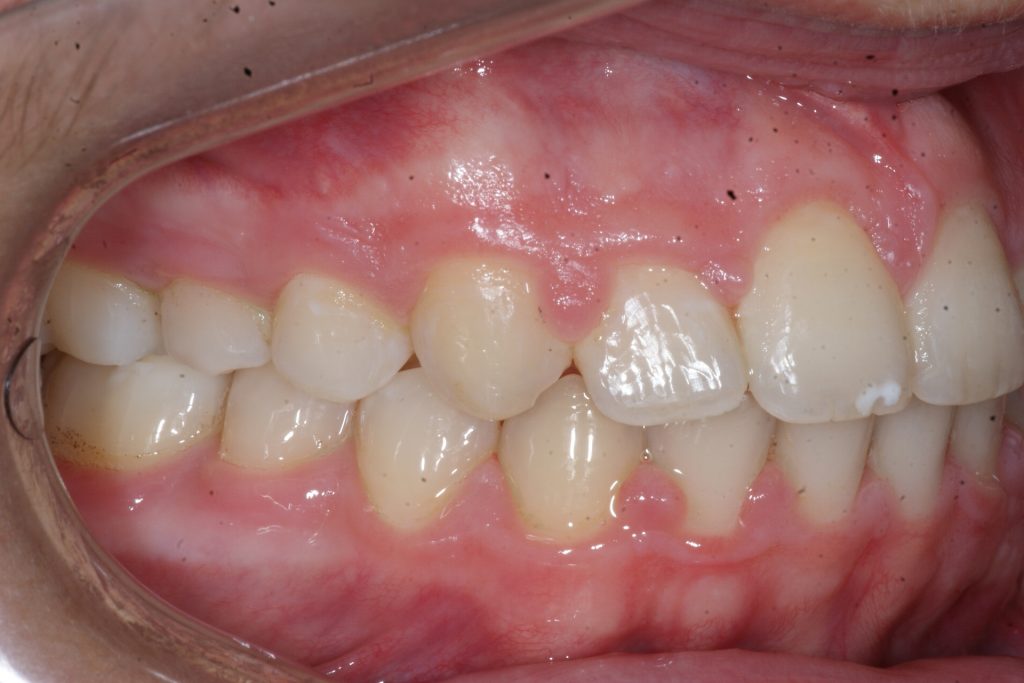

Correction d’une malocclusion de type Classe II.  Des appareils fixes (boîtiers) et une expansion palatine furent nécessaires pour améliorer ce sourire.  Traitement chez un adolescent, réalisé en 21 mois.